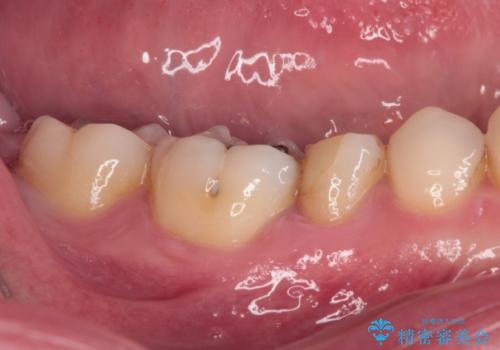

繰り返す痛み 下顎小臼歯の再根管治療

- 定期的に膿の出口ができ、食事の度に痛みを感じるとのことで来院された患者様です。

以前通われて医院にて、再度根管治療が必要であると伝えられていたようですが、レントゲン写真などの診察を行った結果、再根管治療が必要な状態でした。

レントゲン写真より、当該歯周囲に大きな透過像があり、歯槽骨が炎症により吸収している様子が認められます。

根管治療を行った歯はクラウンによる補綴治療が望ましく、来院時にはクラウンが装着されていなかったため、根管治療を再度行いやすい環境でした。